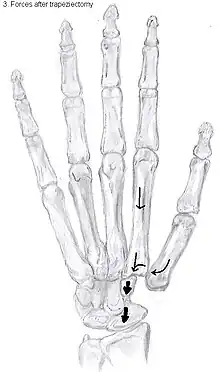

Showing the forces after trapeziectomy

In one randomized trial comparing trapeziectomy alone with trapeziectomy with ligament reconstruction and trapeziectomy with ligament reconstruction and tendon interposition, patients evaluated 5 to 18 years after surgery had similar pain intensity, grip strength and key and tip pinch strengths after each procedure.[25] Trapeziectomy alone is associated with fewer complications than the other procedures.